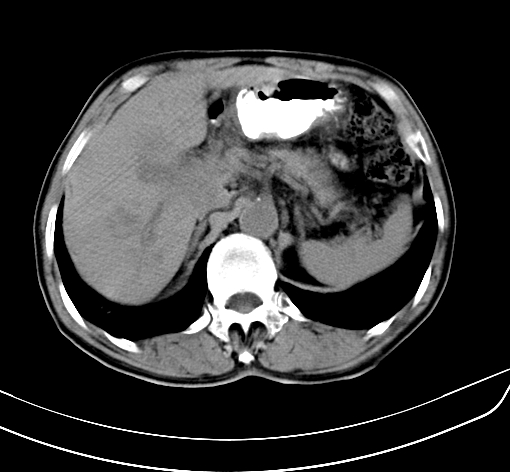

病人 男 70 咳嗽 胃部不适 2月余

胆囊壁增厚,与临近肝实质边界不清,临近肝实质内可见大片边界不清之低密度区,肝门区密度亦有减低,部分结构不清,尾叶前方可见块状影,肝右叶可见多枚边界不清之圆形低密度区,肝内胆管扩张征象,结合病史考虑1胆囊癌肝内转移,肝门区淋巴结转移,门脉癌栓待排2肝内胆管扩张3建议增强扫描

肝脏多发大小不等低密度灶,边界不清,肝门区结构不清,肝内胆管轻度扩张,胆囊密度不均匀,内见软组织样密度影,与相临肝脏边界不清.考虑:1、胆囊ca侵犯肝脏并肝内多发转移,肺上也有结节影,转移?建议强化扫描.2、胃充盈不好,如怀疑有病变最好建议做相关检查.

胆囊壁增厚,周围模糊不清,肝内多发低密度影,胃充盈欠佳,胃壁增厚,外形尚规整,考虑胆囊炎、胆囊癌肝内转移?建议胃肠道进一步检查或增强扫描。